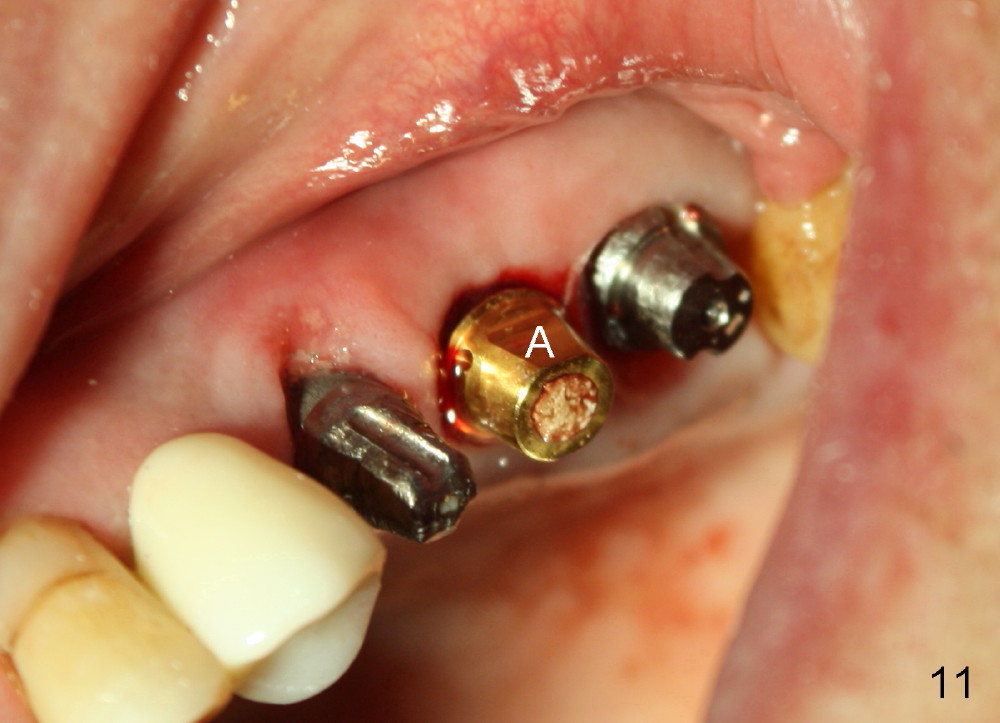

The provisional dislodges once more several days later.  The implant at the site of #14 is uncovered; an abutment (A) is placed (Fig.10.11); a provisional (Fig.12 P) 3-unit bridge is fabricated and cemented securely.  There is some occlusal contact with the opposing teeth.